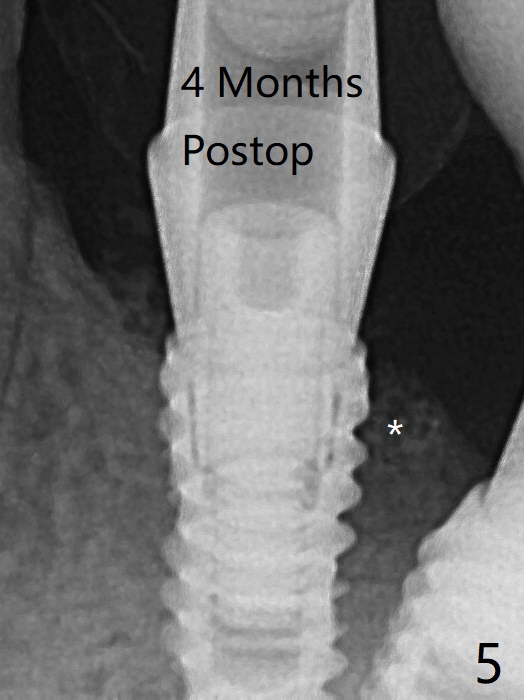

尽管术后即刻牙槽嵴放置粘性骨粉(图一:*),术后4个月远中牙槽嵴稍微下降(图五:*)。